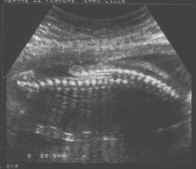

- Modifications sous tentorielles :

- Grande citerne inexistante,

- Vermis inférieur ectopique,

- Hémisphères cérébelleux attirés vers le bas formant une incurvation à concavité antérieure se moulant sur le tronc cérébral.

cliché droit

- V4 aplati, étiré,

- Horizontalisation de la tente du cervelet sur une coupe frontale postérieure céphalo-caudale.